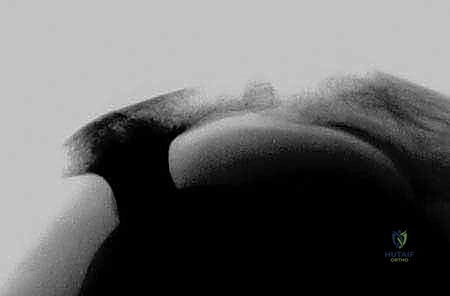

الكفة المدورة ليست مجرد وتر واحد، بل هي شبكة معقدة وديناميكية من الأوتار والعضلات التي تغلف رأس عظم العضد (مفصل الكتف)، وتوفر له القوة الهائلة والثبات الميكانيكي اللازمين للقيام بكافة الحركات اليومية، بدءاً من رفع كوب من الماء، تمشيط الشعر، وصولاً إلى ممارسة الأنشطة الرياضية المعقدة والأعمال الشاقة.

هذه المنظومة تعمل بتناغم مذهل لإبقاء رأس عظم العضد ثابتاً في تجويف الكتف الضحل (الحُق)، مما يمنح الكتف أوسع مدى حركي لأي مفصل في جسم الإنسان. ولكن، هذه الحرية في الحركة تأتي على حساب الاستقرار، مما يجعل الأوتار عرضة للضغط، الاحتكاك، والتمزق.